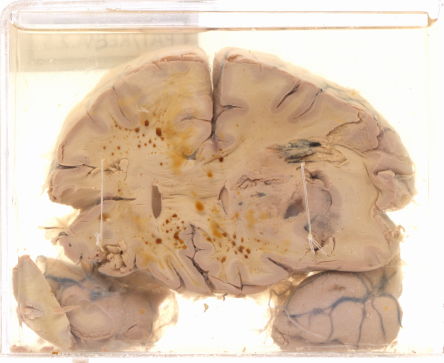

A.2.5 Intra cerebral haemorrhage

Coronal section of the cerebrum

Haemorrhagic areas in the parietal lobe causing compression of the adjacent ventricle.